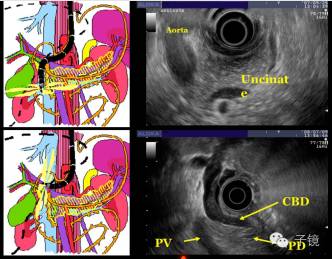

EUS是诊断胰腺疾病非常重要的工具。有环扫EUS和扇扫的EUS。

EUS+EUS-FNA是胰腺癌最重要的检查方法。

1、如果CT怀疑胰腺有肿块,但不能确认的话,建议行EUS,必要时行穿刺,便可以确诊。

陈洪潭教授:感谢李教授,对胰腺癌早期诊断这么精彩、全面的讲解,很详细。首先李教授提出胰腺癌发病率不高,但死亡率非常高的现状。胰腺癌发病、发展有一个过程,从正常到早期癌变,要11.7年左右的时间,从不典型增生到1期癌有6.8年的时间给我们去发现和诊断胰腺癌。发现胰腺癌影像学非常重要。常规的检查包括有CT、B超、MR等,但诊断率欠精准,EUS是发现早癌胰腺癌非常重要的武器。EUS就是超高分辨率,可以放在胃内,对1.5cm以下病灶可以发现,建议平时要多开展超声内镜。慢性胰腺炎会对EUS出现干扰,出现假阴性或假阳性,可以通过超声造影解决。李教授能做到5mm的小病灶进行穿刺,确实很不了起。个人认为对胰头、体、尾都能穿刺成功,这点可能有一定的难度,需要与用心操作,不断积累经验,提高穿刺成功率。对哪些病人需要做EUS,李教授也做了很详尽的讲述,第一是家族史、第二是长期吸烟、肥胖者,第三是糖尿病,有部份糖尿病人就是胰腺癌的症状之一,还有基因异常,胰腺囊肿,慢性胰腺炎等都是需要重视的病因。我们在临床工作中的重点是尽量发现一些胰腺早癌,要有一颗象发现胃肠道早癌热心去用心发现。建议只要有高危因素就建议筛查,尽量用EUS筛查。